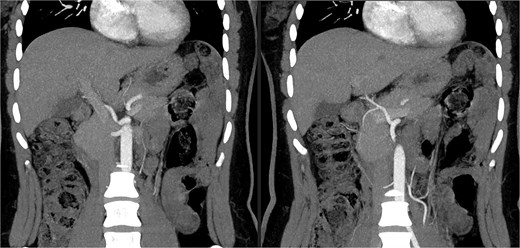

A 27-year-old woman, with no notable medical history, was evaluated as a living donor for her 9-year-old son with hepatic failure. The preoperative workup included an abdominal-pelvic CT angiogram and a biliary MRI. The biliary MRI showed normal biliary ducts. However, the CT angiogram revealed a significant vascular variation: the absence of the typical celiac trifurcation (Figs 1 and 2). The celiac trunk gave rise only to the left gastric artery and the splenic artery, forming a gastrosplenic trunk, while a second arterial trunk originating from the abdominal aorta at the level of L1 simultaneously gave rise to the SMA and the CHA: a hepatomesenteric trunk.

CT angiogram showing the celiac trunk giving rise to the left gastric artery and splenic artery, along with the hepatomesenteric trunk.